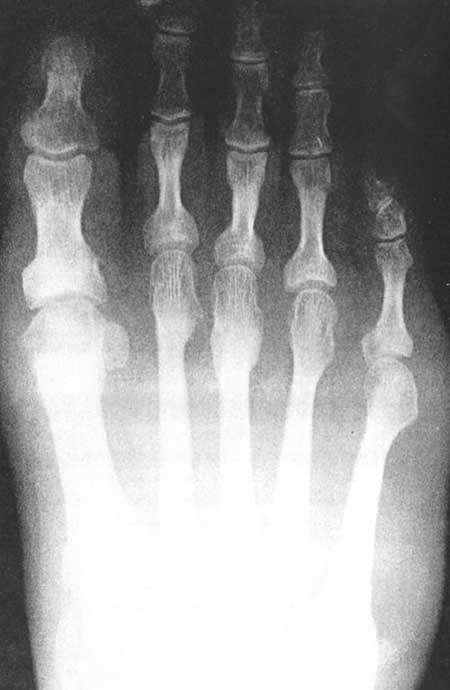

Fig 3A. (pre-operative)

|

Fig 3A (post-operative)